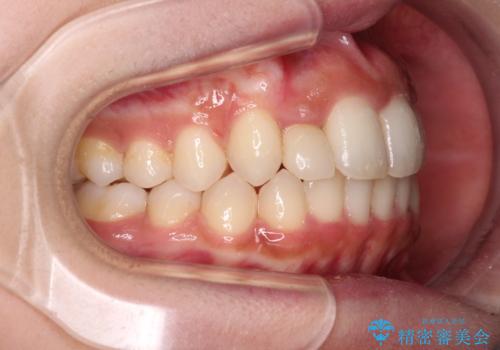

抜けてしまうと言われた前歯 インビザラインによる矯正治療

- 上下前歯のデコボコを気にして来院された患者様です。

前歯のセラミックが装着されている歯は、歯根が短くなっており、他院では抜けてしまうので矯正はできないと言われていたようです。

患者様と相談し、抜けてしまった場合にはインプラントあるいはブリッジによる補綴治療が必要となることを確認し、極力歯根に負担のかからないような仕上がりで治療を進めて行くこととしました。

デコボコを解消には、IPR(歯と歯の間を削る)をメインに歯列排列を設計し、インビザラインにて矯正治療を行うこととしました。

レントゲン写真上では、矯正治療前後で歯根長さに大きな違いはなく、抜歯を回避することができました。

上顎内側に転位している前から2番目の歯は移動が難しく、無理矢理歯根全体を動かそうと設計すると、歯肉退縮・歯髄壊死・歯根吸収といった危険性が増すため、無難なゴールにて治療を終えることとなりました。